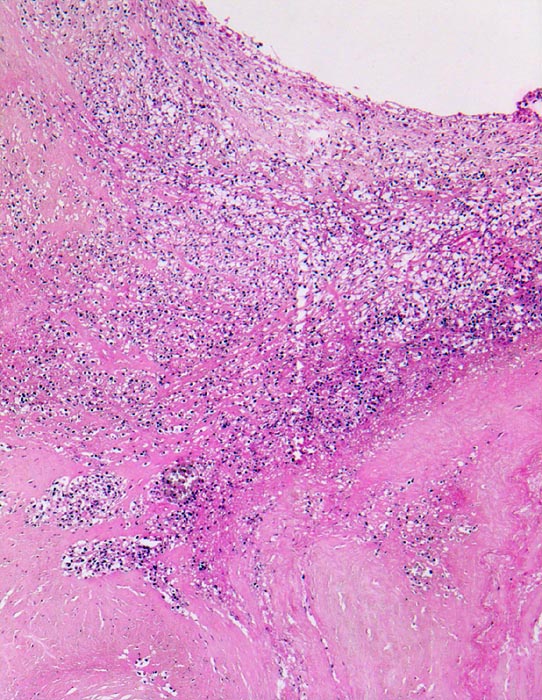

Endocarditis ulcero-polyposa der Aortenklappe

Entzündung infektiös

Aortenklappe

In dem Zwickel zwischen noch erhaltener Klappe und Polyp beginnende Granulationsgewebsbildung.

Akut einsetzendes Krankheitsbild mit Fieber, Schüttelfrost, Müdigkeit und Dyspnoe. Blutkulturen wiederholt positiv für Staphylokokkus aureus. Keine Klappenvorschädigung bekannt.

Histologie

50